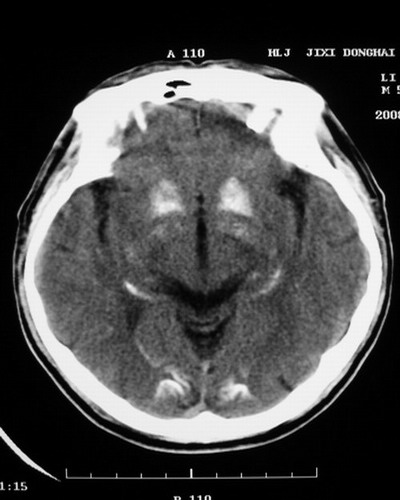

以下是引用随光逐影在2008-1-14 17:26:00的发言:[br]考虑为:甲状旁腺功能低下。需与fahr`s病相鉴别。建议:实验室检查。